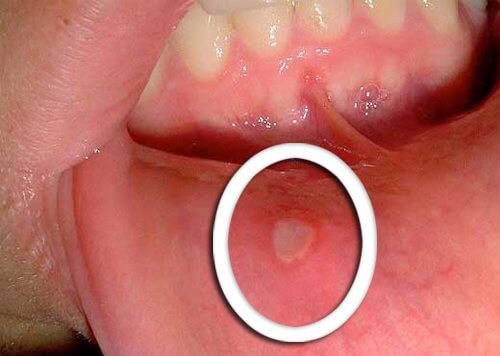

Physical changes in the mouth

- The earliest symptom of oropharyngeal cancer are little sores that do not heal.

- Red or white blotches typically appear on the tongue, the gums, or the lips.

- Be aware of any unusual changes that don’t improve in a few days and bring them to the attention of your doctor.